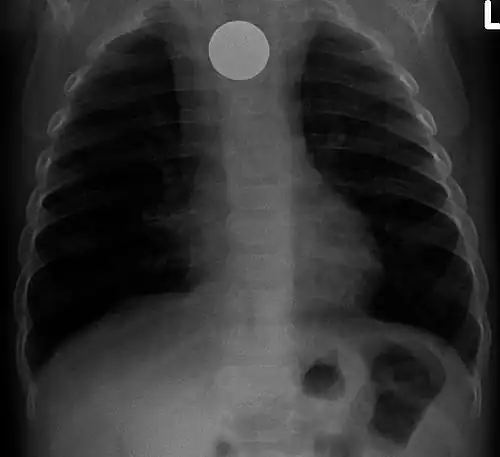

Chest radiograph showing a Venezuelan 25 cent coin lodged in the upper esophagus of a 9-year-old girl. -

A coin seen on AP CXR in the esophagus -